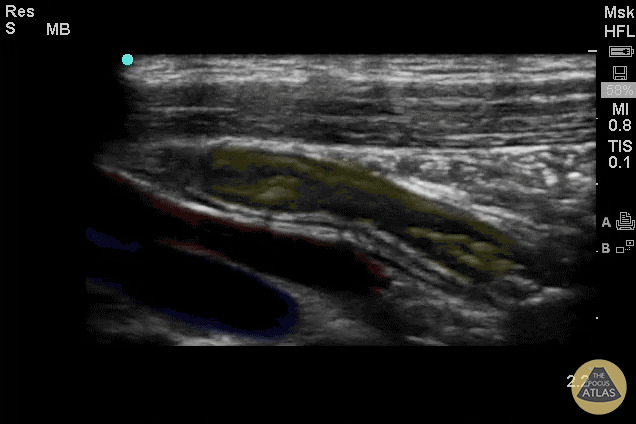

Colorized Appendicitis - Colorized Appendix with Landmarks (Longitudinal)

Yellow = Appendix Red = Iliac Artery Blue = Iliac Vein Images provided by Sathya Subramaniam - Children’s Hospital of Philadelphia, edited by Matthew Riscinti - Kings County Emergency Medicine